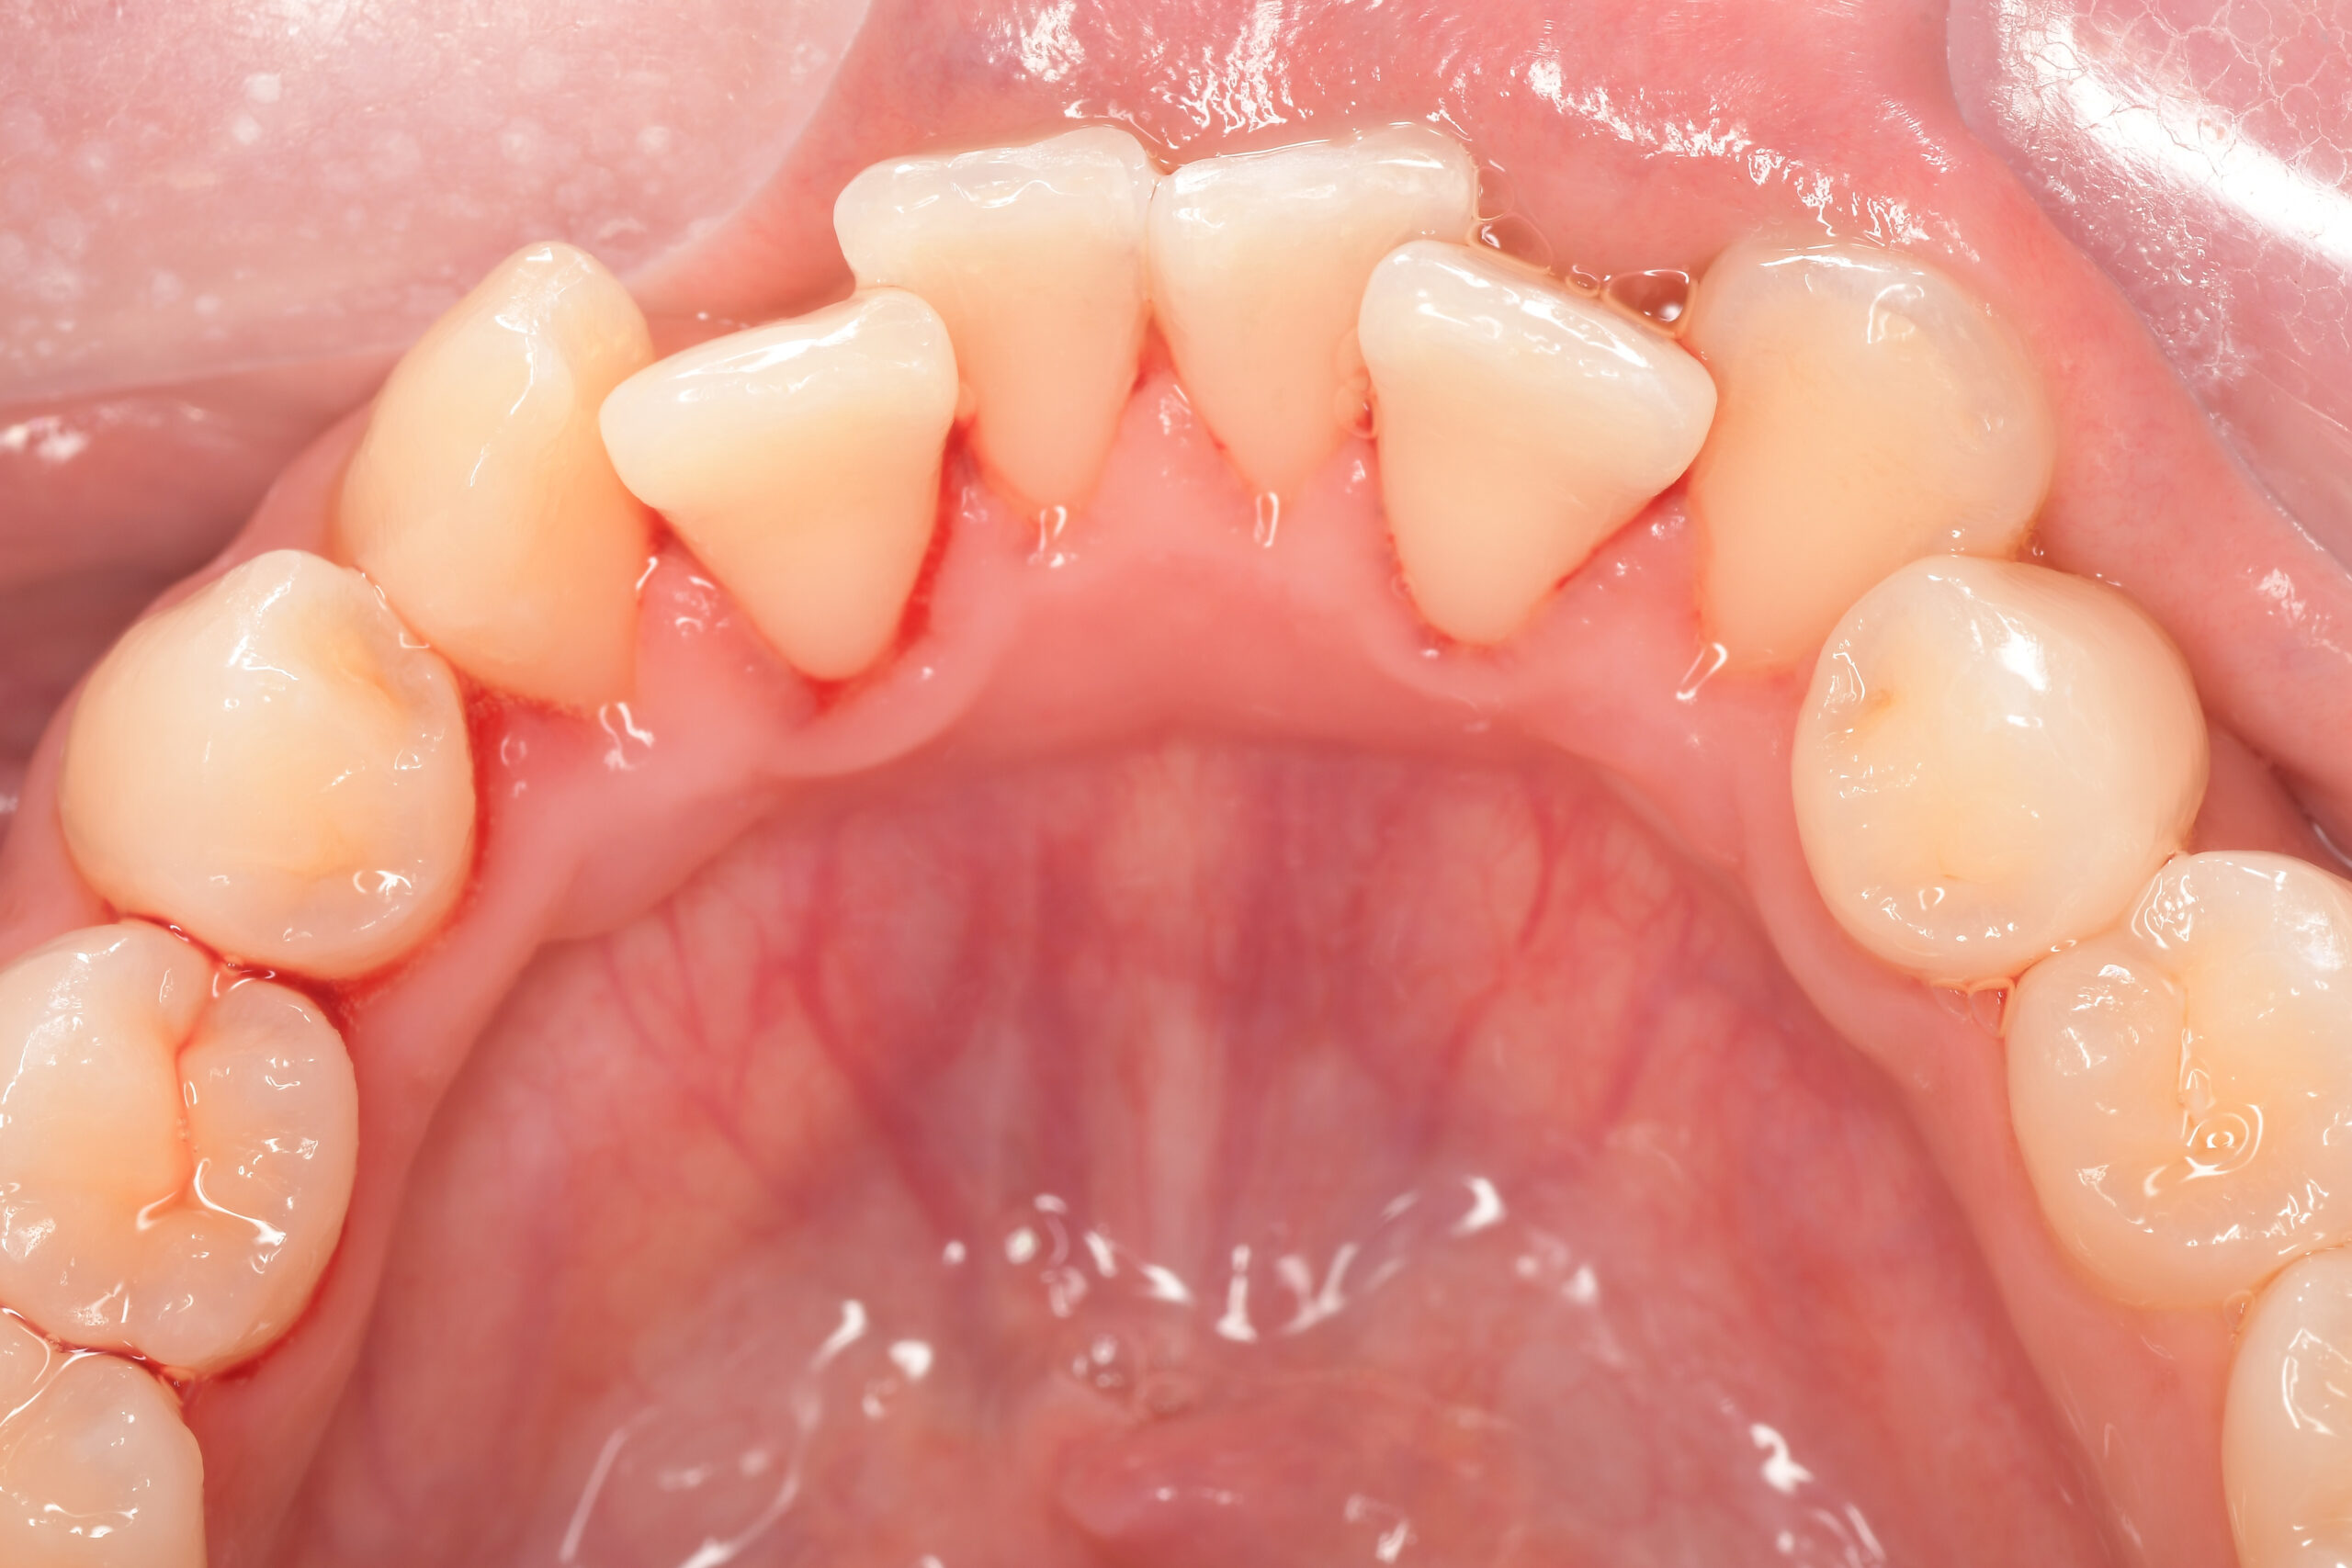

CASE 10

Before①

After①

Before②

After②

基本情報

| 年齢・性別 | 38歳・男性 |

|---|---|

| 主訴 | 下顎 歯石除去したい |

| 治療内容 | スケーリング |

| 治療期間 | 30分 |

| 治療費 | 約1,500円(保険診療) |

| リスク・副作用 | 知覚過敏、歯肉退縮 |

| 治療方針 | 歯肉縁上歯石を除去してから歯肉縁下歯石を除去します。ご自身でのプラークコントロールができるようになったら定期検診に移行します。 |

| 担当者所見 | 半年ぶりの歯科医院の受診。歯石が付きやすいためセルフケアの重要性をお伝えして、定期的にクリーニングを行います。出血率が高く炎症が強いため、今後はセルフケアを強化して歯周病治療を行います。 |